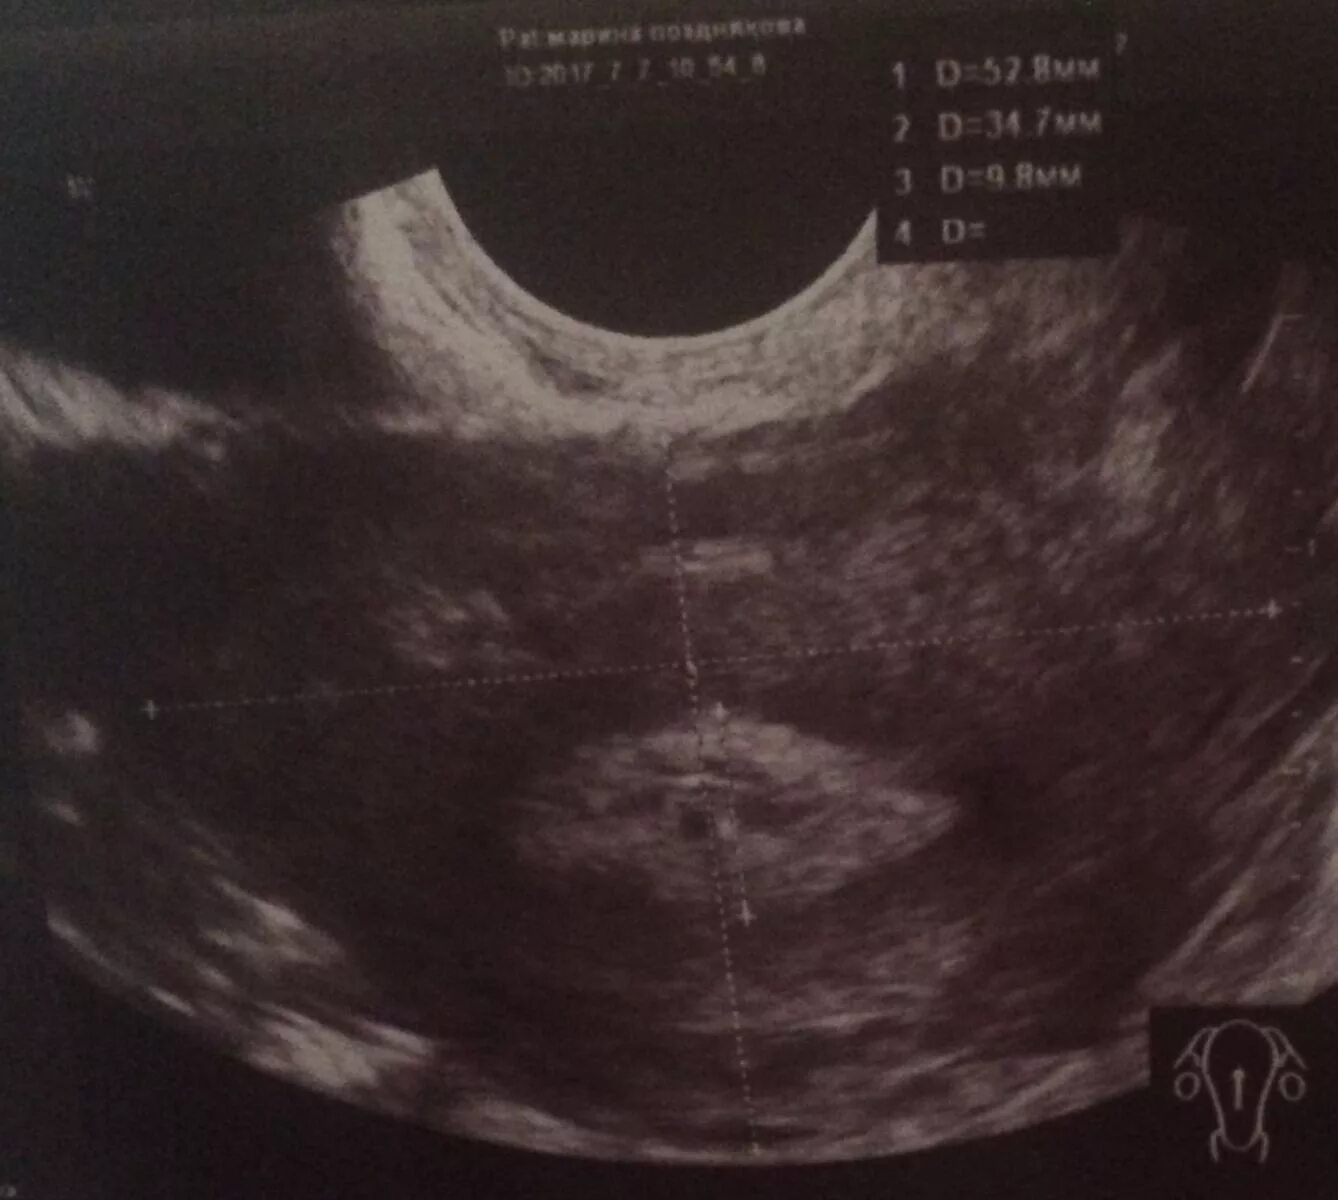

Тест положительный узи не видит